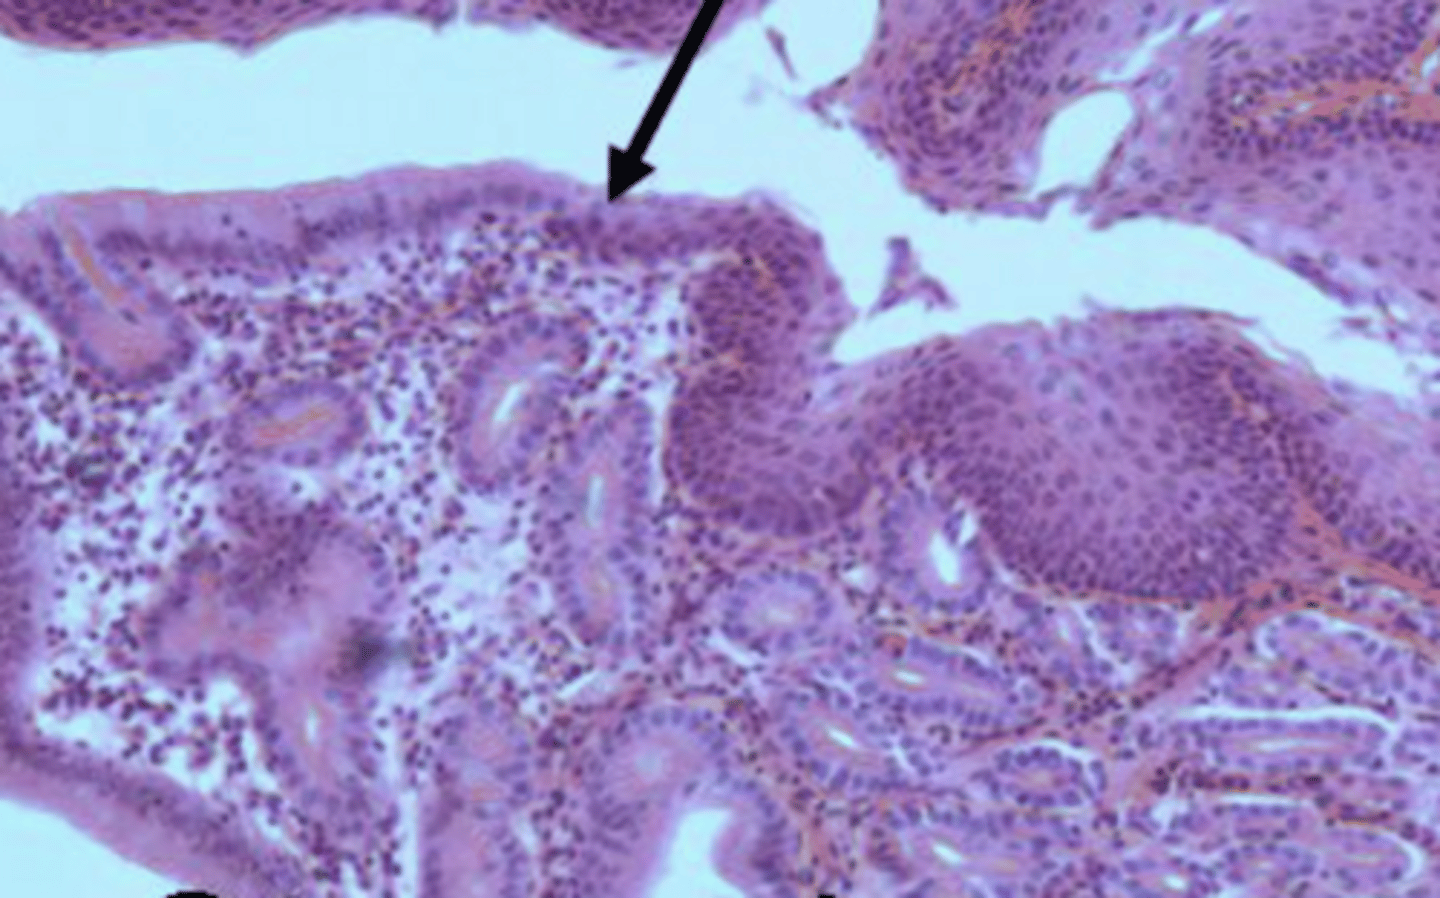

villi of small intestine

Peyer's patches of ileum